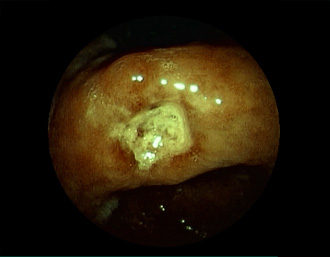

症例1:胃潰瘍(37才、男性)

①胃潰瘍(Stage A1)

健診:胃レントゲン検査で、胃角部ニッシェを指摘され当院受診。

胃角部小弯に、深くて大きな、大きさ約10mmの胃潰瘍(stage 1)

があり、潰瘍底は一部白苔はみ出しを認める。エソメプラゾールマグネシウム水和物投薬で治療開始しました。

(FICE画像)